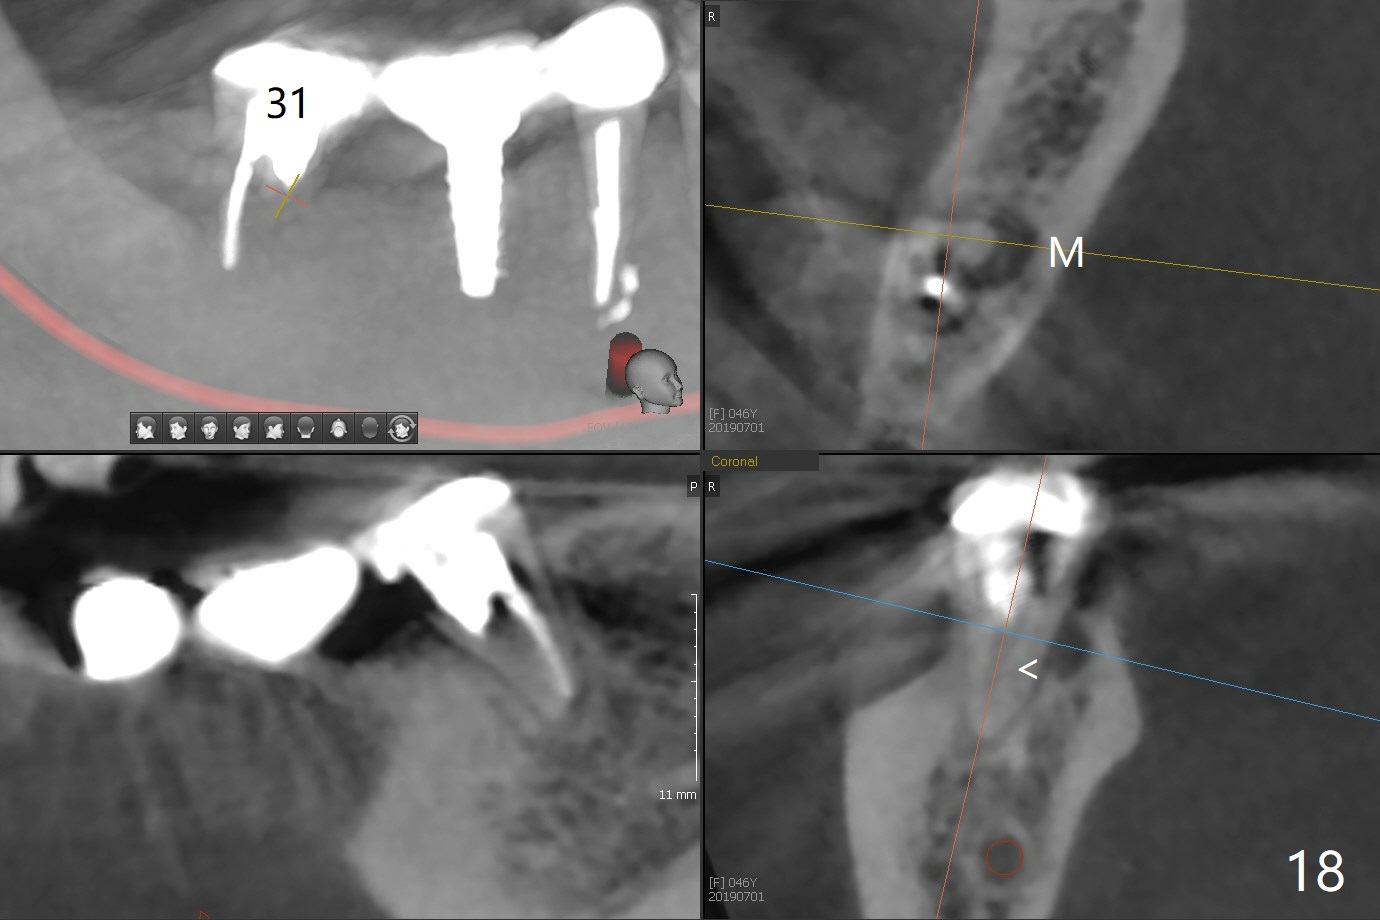

Splinted provisional is fabricated #30 and 31 one month postop. The patient returns for final restoration (single units) nearly 4 months postop (Fig.11). Since the margin is subgingival, a screw type crown is fabricated for #30 (Fig.12). The buccal gingiva looks convex after healing cap removal (Fig.13, as compared to Fig.4 (concave)). PA is taken immediately post tightening and cementation (Fig.14, 5 months postop). It appears that new bone has grown between the most coronal threads (arrows). The bone density immediately around the implant appears to increase 1.5 years post cementation (Fig.15,16). She returns because of failure of 18-20 bridge (implants will be placed at 18/19). The implant at #30 is in fact not placed deep enough; the coronal threads seem to be exposed, although there is no periimplantitis (Fig.17 CT). The tooth #31 is symptomatic; the mesial canal is missing (Fig.18 M, <). The gingiva around the crowns at #30 and 31 remains healthy 2 years 4 months post cementation (Fig.19). Metal exposure of the crown at #31 is intentional. Occlusal reduction is done to alleviate periapical re-infection (Fig.18).